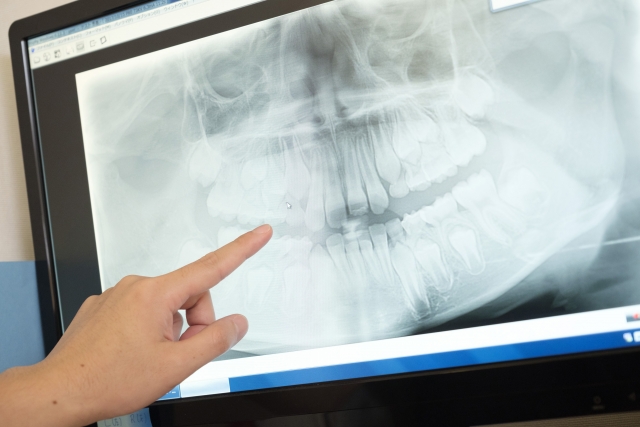

レントゲン撮影による発育への影響...